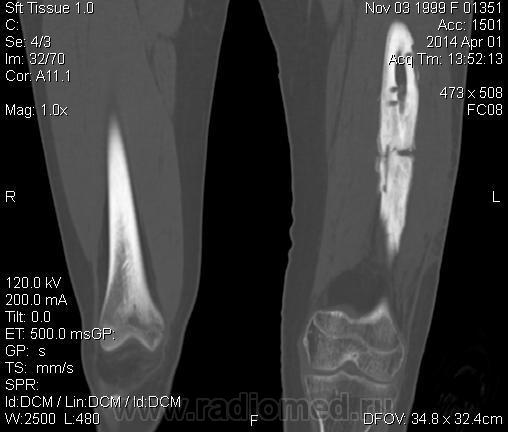

Молодая дама (14 лет) с переломом срдней трети диафиза левого бедра в анамнезе (декабрь 2012 г). Ломала ногу несколько раз в этом месте. Сейчас состояние после МОС. Как следует понимать изменения в кости, формируется ли ложный сустав?

Похоже ложный сустав сформировался. Но при нём обычно большие напластования костной мозоли, здесь их нет. В таких случаях смотрю при скопии подвижность.

Ох, не хочется думать о ложном суставе в 14 лет... По срокам под ложный сустав подходит, он характеризуется замыканием костномозгового канала с формированием подобий суставных поверхностей. У нее же есть хиленькая периостальная костная мозоль по задней поверхности бедра удерживающая отломки в правильном положении. Я склонна думать, что это скорее застарелый перелом (оно же замедленная консолидация). Здесь очень важно посмотреть предыдущие снимки (поиск рефрактуры, либо отсутствия полной консолидации).

Настоящего, родного ложного сустава пока нет, хотя костномозговой канал дистального отломка уже закрыт - образовалась склерозированная замыкательная пластина. Варусная деформация почти в 165 градусов... Я бы заключилась неполной консолидацией и варусной деформацией, прогностически формирование ложного сустава очень вероятно.